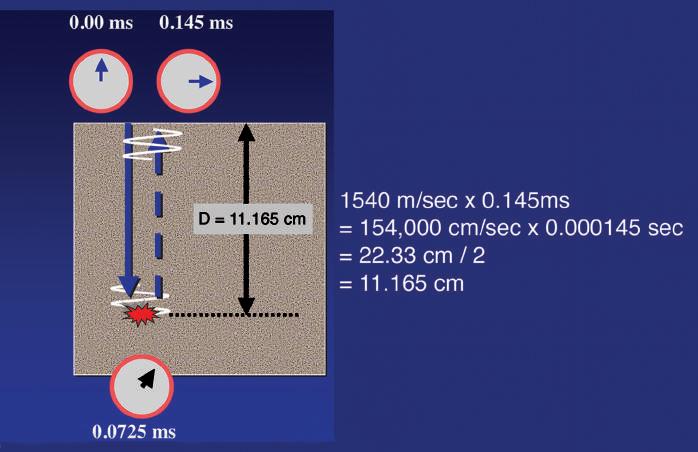

Propagation velocity is a particularly important value in clinical ultrasound and is critical in determining the distance of a reflecting interface from the transducer. Much of the information used to generate an ultrasound scan is based on the precise measurement of time and employs the principles of echo-ranging (Fig. 1.4). If an ultrasound pulse is transmitted into the body and the time until an echo returns is measured, it is simple to calculate the depth of the interface that generated the echo, provided the

propagation velocity of sound for the tissue is known. For example, if the time from the transmission of a pulse until the return of an echo is 0.000145 seconds and the velocity of sound is 1540 m/ sec, the distance that the sound has traveled must be 22.33 cm (1540 m/sec × 100 cm/m × 0.000145 sec = 22.33 cm). Because the time measured includes the time for sound to travel to the interface and then return along the same path to the transducer, the distance from the transducer to the reflecting interface is 22.33 cm/2 = 11.165 cm. By rapidly repeating this process, a two-dimensional (2-D) map of reflecting interfaces is created to form the ultrasound image. The accuracy of this measurement is therefore highly influenced by how closely the presumed velocity of sound corresponds to the true velocity in the tissue being observed (see Figs. 1.2 and 1.3), as well as by the important assumption that the sound pulse travels in a straight path to and from the reflecting interface.

FIG. 1.4 Ultrasound Ranging. The information used to position an echo for display is based on the precise measurement of time. Here the time for an echo to travel from the transducer to the target and return to the transducer is 0.145 ms (0.000145 seconds). Multiplying the velocity of sound in tissue (1540 m/sec) by the time shows that the sound returning from the target has traveled 22.33 cm. Therefore the target lies half this distance, or 11.165 cm, from the transducer. By rapidly repeating this process, a two-dimensional map of reflecting interfaces is created to form the ultrasound image.